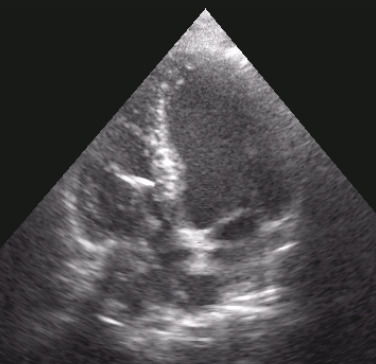

Endocardite infettiva su elettrocatetere stimolatore abbandonato

Andrea Barbieri